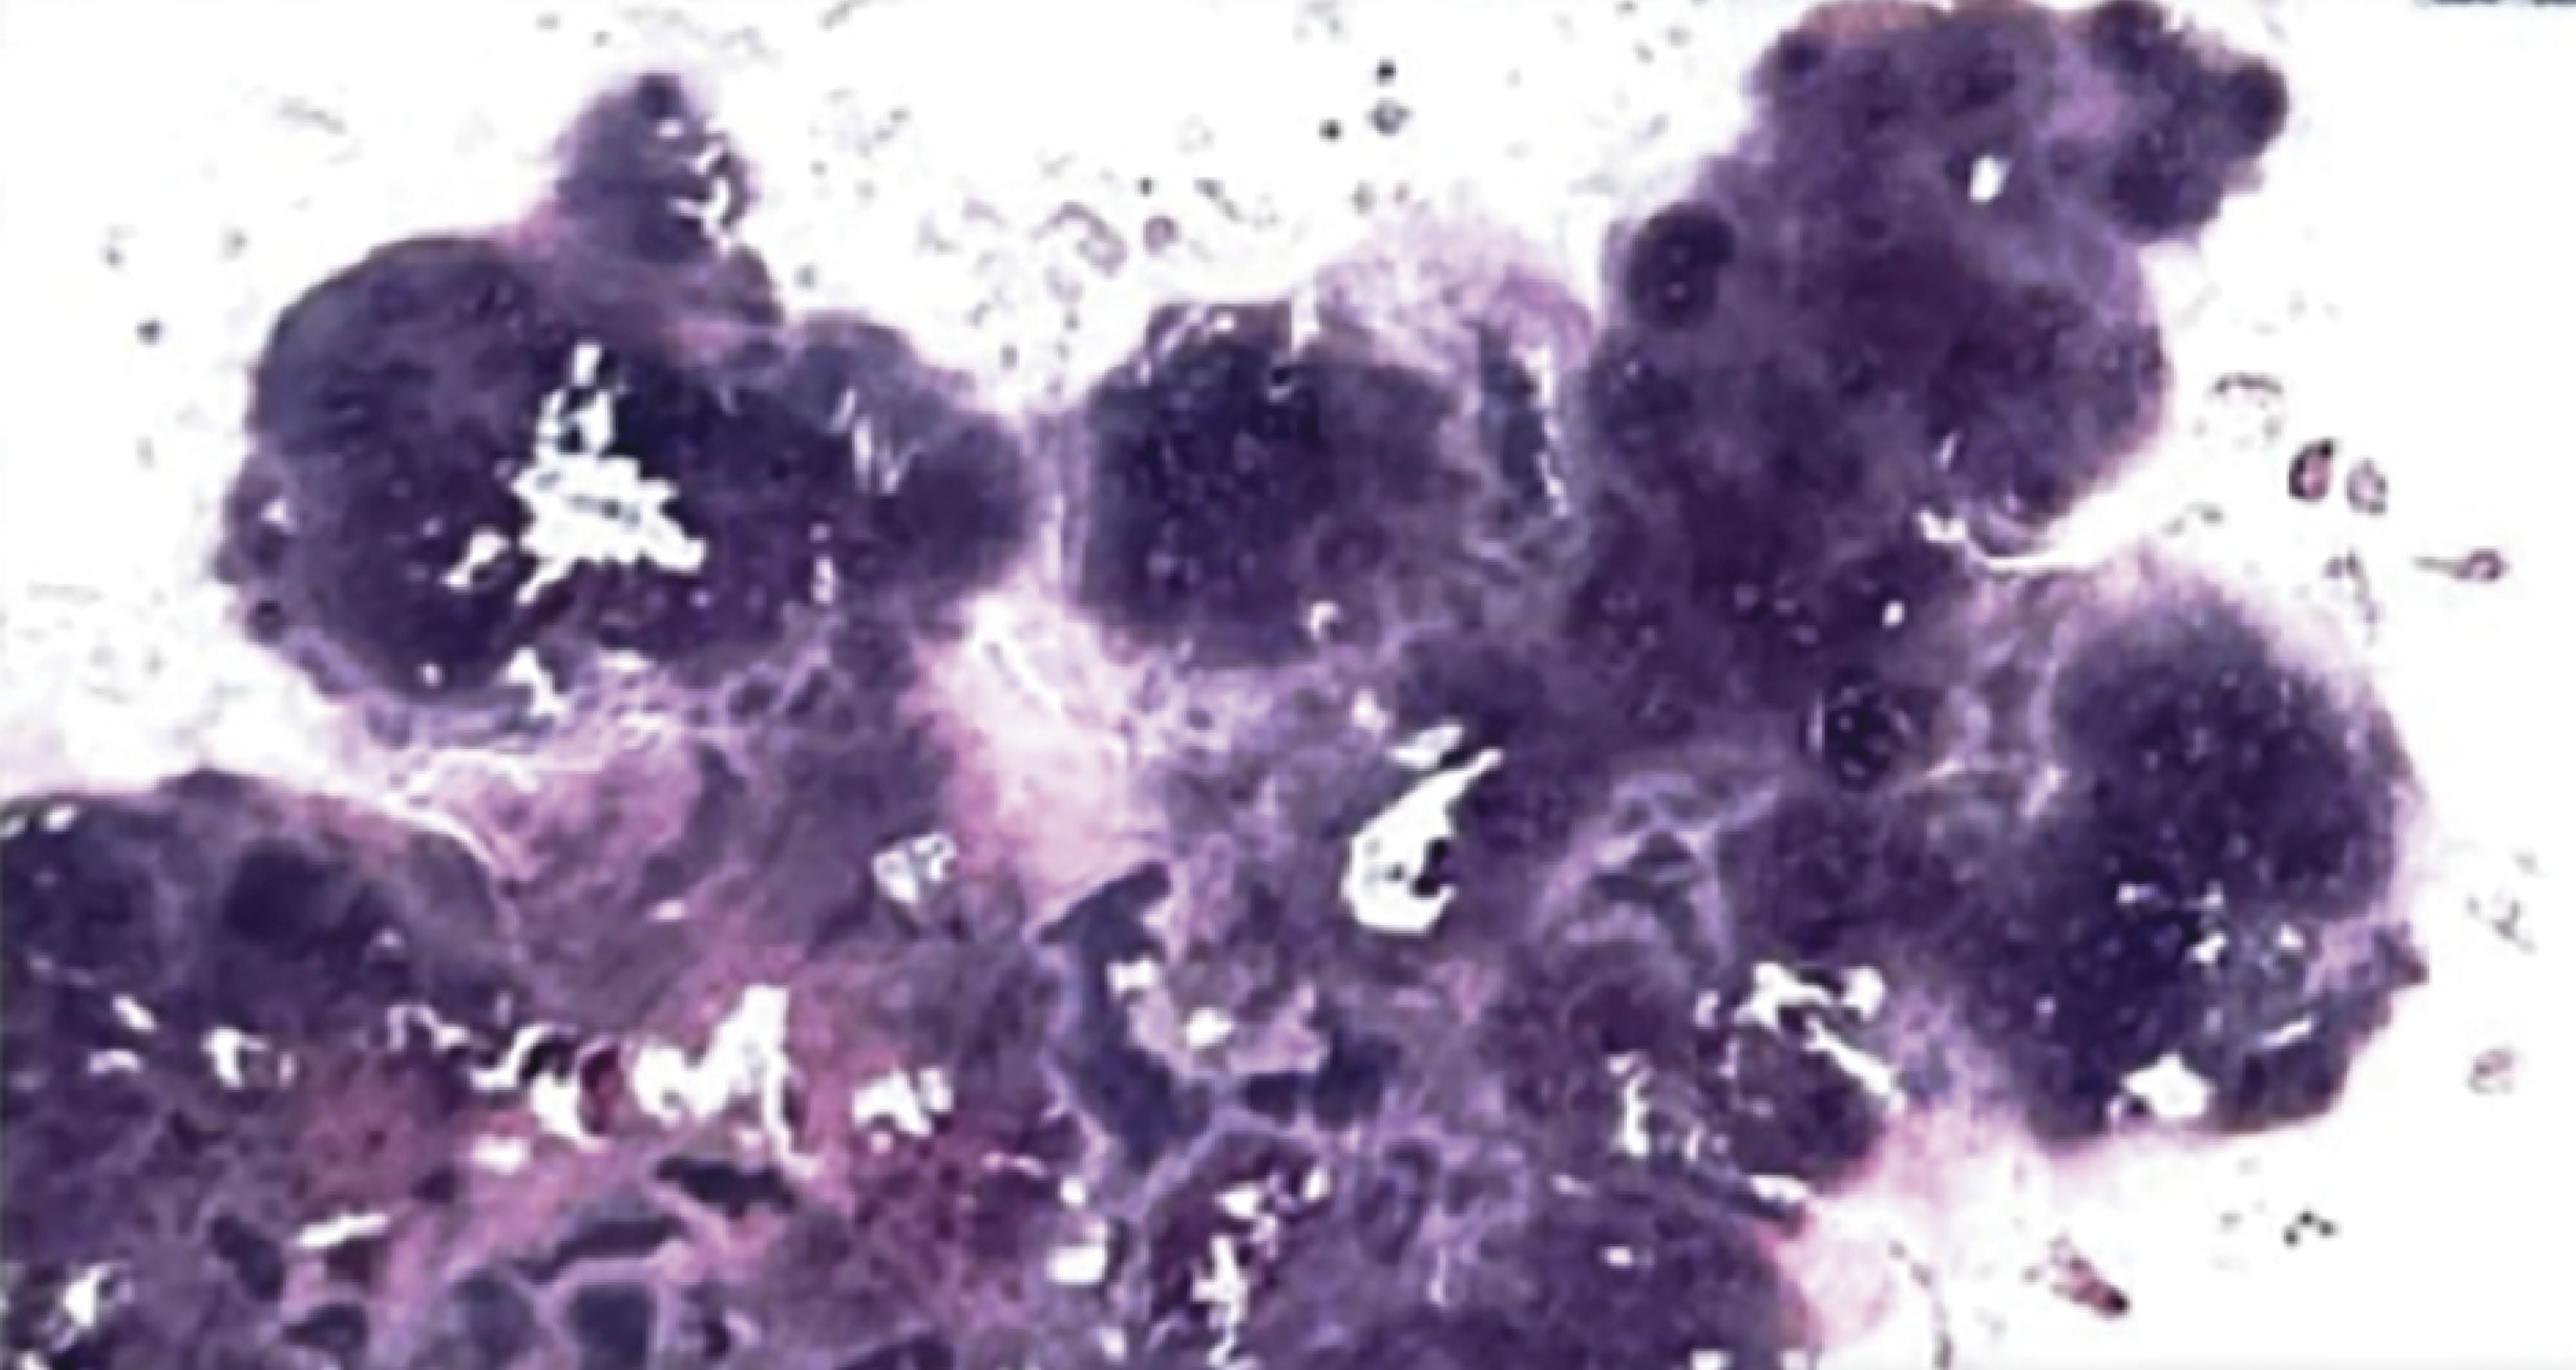

PRESENTACIóN DEL CASO

Masculino de 54 años, que consulta por dolor, bloqueos al momento de flexionar y extender la rodilla izquierda de dos años de evolución sin antecedentes de trauma. Se evalúa marcha dolorosa acompañado de edema y dolor en rodilla izquierda. La resolución del caso se realizó mediante cirugía: artroscopia de rodilla con resección completa de la condromatosis sinovial (Figuras 1, 2 y 3).

Figura 1

Figura 2

Figura 3